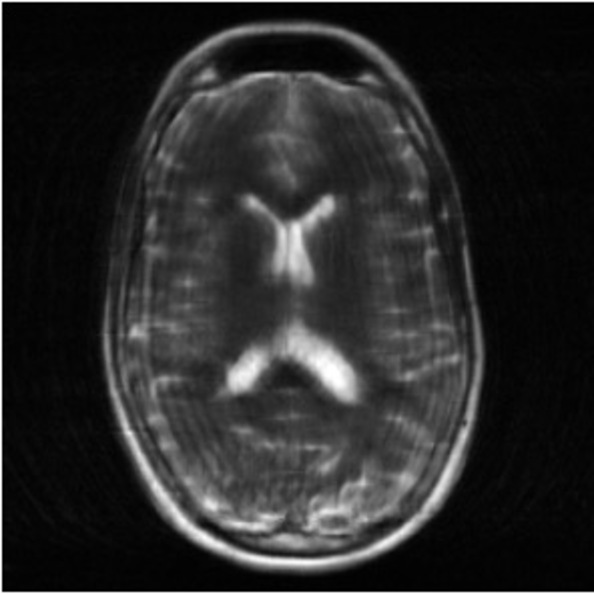

Figure 2: Example MRI magnitude reconstructions with S=25S=25 training slices at acceleration factor R=7R=7. PaDIS-MRI reconstructions are sharper and more faithful to the fully-sampled ground truth. Insets are shown to highlight detail.

Figure 2 provides a visual comparison of the reconstruction quality of each method on example slices. In reconstructions from the S=25,R=7S=25,R=7 models, FastMRI-EDM exhibits slightly more blurring and loss of fine structural details, particularly in regions with complex anatomical features. PaDIS-MRI, in contrast, preserves sharper boundaries and finer details. This enhanced data efficiency can be attributed to the patch-based prior’s ability to learn localized structural motifs more effectively from limited examples. Figure 6 in the Appendix shows similar reconstructions at S=200,R=7S=200,R=7 where FastMRI-EDM more closely approaches the performance of PaDIS-MRI but still struggles with highly detailed anatomy. At both dataset sizes, MoDL underperforms the diffusion priors. In Figure 2, MoDL’s FLAIR reconstruction exhibits pronounced artifacts, likely reflecting reduced generalizability of a supervised prior when the training distribution underrepresents FLAIR.